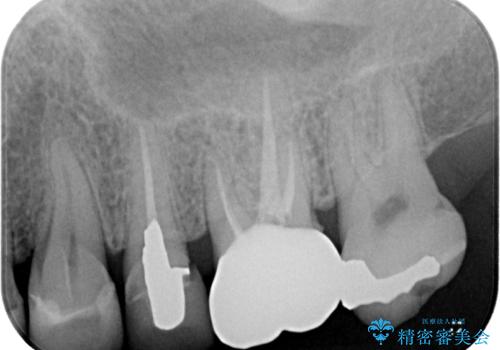

- 銀歯が取れたとのことで来院された患者様です。患者様の歯をあまり削りたくないというご希望に添い、セラミックインレーにて治療を行うこととなりました。

拡大鏡視野下で、保険のプラスチック、虫歯の除去を行い、セラミックインレーに適した形に整えました。

歯と歯茎の間に圧排糸と言われる糸を入れてシリコーン印象材にて精密な型どりをしました。

セラミックインレーの装着時には、唾液の侵入を防ぐために、ラバーダム防湿を行いました。